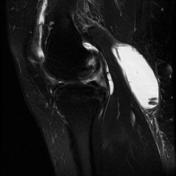

Một số hình ảnh

Hình ảnh siêu âm, MRI